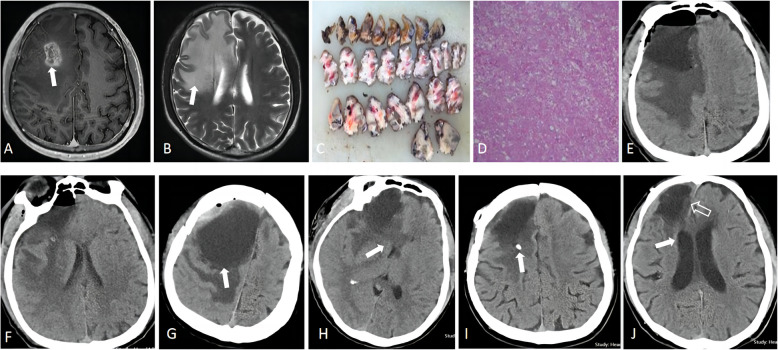

Background: The postoperative space-occupying cyst (SOC) in the Tumor bed is rarely reported, and they are easily overlooked in the early stages. This oversight may result in serious consequences. This study aimed to systematically analyze the clinical characteristics and principles of managing SOC.

Method: We conducted a retrospective analysis of clinical data on postoperative Tumor bed SOC at our institute. Comprehensive searches of English literature were performed on PubMed and Web of Science databases, while Chinese literature searches were conducted on the China National Knowledge Infrastructure and Wanfang Database, with a cutoff date of August 2024. Results Among 1026 brain Tumor resections performed at our institute, 10 patients (0.97%) had tumors situated in the supratentorial area. Four (40%) patients were managed with external drainage using an Ommaya reservoir placed in the cystic cavity, while six (60%) underwent direct percutaneous puncture drainage. A favorable prognosis was observed in all treated cases. A total of 106 cases were documented in both Chinese and English literature, yielding an incidence rate ranging from 0.04% to 4%. Percutaneous puncture external drainage was the predominant intervention, performed in 47 cases, representing the highest percentage at 44.3%. A favorable prognosis was observed in 78.1% (82/105) of treated cases, with four reported deaths.

Conclusions: Supratentorial brain tumors situated within the cerebrospinal fluid circulation may give rise to SOC after resection. Following aggressive treatment, most patients experience a favorable prognosis.